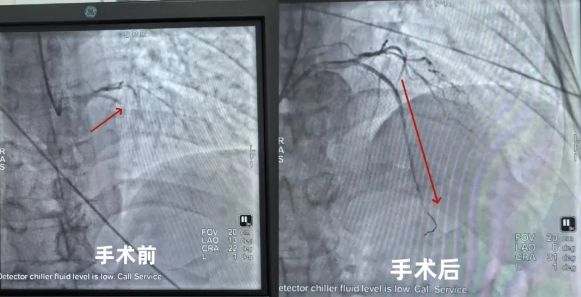

近日,淄博市第四人民医院心血管内科收治了一名急性广泛前壁心肌梗死的患者。患者老年男性,因剑突下持续疼痛15小时入院,入院时BP171/102mmHg,全身大汗淋漓,神志清,精神差,心电图检查提示:窦性心律,左前分支阻滞,V1-V6 导联 ST 段抬高;心肌标志物三项显示高敏肌钙蛋白T943.0pg/mL↑,肌酸激酶同工酶>300ng/ml↑,N端脑钠钛前体1256pg/ml↑。结合患者持续性胸痛表现,心电图及心肌损伤标志物检查结果,诊断为急性广泛前壁心肌梗死。患者存在生命危险随时可能出现呼吸心脏骤停,心内科副主任张敏慧与主治医师姜丽丽迅速启动应急预案,立即联系导管室行急症经皮冠状动脉介入治疗(PTCA+PCI),穿刺右桡动脉冠脉造影后提示左冠状动脉前降支近段100%闭塞,为罪犯血管,心内科医疗团队在最短时间内成功将细如发丝的导丝通过前降支闭塞段,并经球囊扩张后成功地开通了一条“生命通道”。

很快,支架被成功植入,堵塞的血管畅通了,患者转危为安,手术过程顺利,术后安返病房。术后患者未再胸痛,心电图提示 ST 段回落,各项指标逐渐好转,回想起整个经过,患者及家属仍心有余悸,如果当时得不到及时救治,后果将不堪设想,患者住院一周康复出院,出院时患者及家属对心内科医疗团队的精湛技术及贴心的护理服务非常满意,给予高度评价。